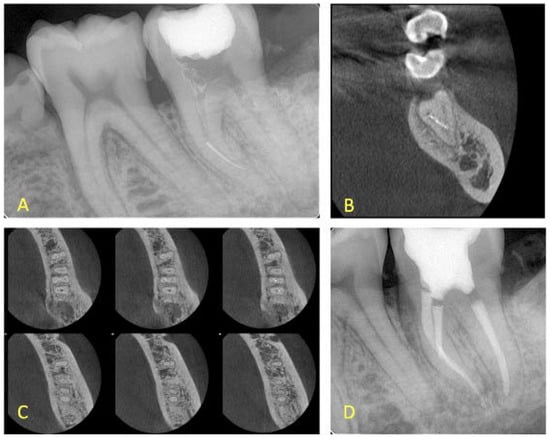

- If a lesion was present, the canals were separate and the fragment was located at the apical level, and a final treatment plan of bypassing the fragment was set (Figure 1).